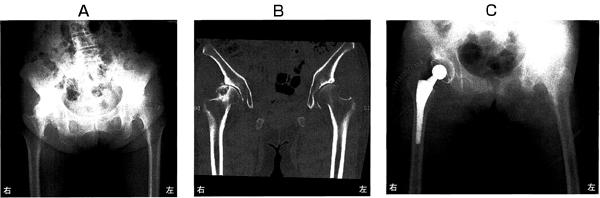

64歳の女性。10年前から歩行時に右股関節痛を生じ、徐々に増悪して歩行が困難となったため後外側アプローチによる人工股関節置換手術を受けた。術前の股関節部エックス線写真(A)、骨盤部CT(B)および術後の股関節部エックス線写真(C)を別に示す。術前に認められないのはどれか。

GV84VrRHp05JT2YM3Li0a

1

骨囊胞

2

骨棘形成

3

臼蓋底の肥厚

4

特発性骨壊死

5

関節裂隙狭小化

64歳の女性。10年前から歩行時に右股関節痛を生じ、徐々に増悪して歩行が困難となったため後外側アプローチによる人工股関節置換手術を受けた。術前の股関節部エックス線写真(A)、骨盤部CT(B)および術後の股関節部エックス線写真(C)を別に示す。術後の理学療法で誤っているのはどれか。

JtbQWhriWRFW3tVyeuZUz

術後2日の大腿四頭筋の筋力強化

術後3日の中殿筋の筋力強化

術後7日の股関節内旋可動域訓練

術後10日の荷重歩行訓練

手術創治癒後の水中歩行訓練